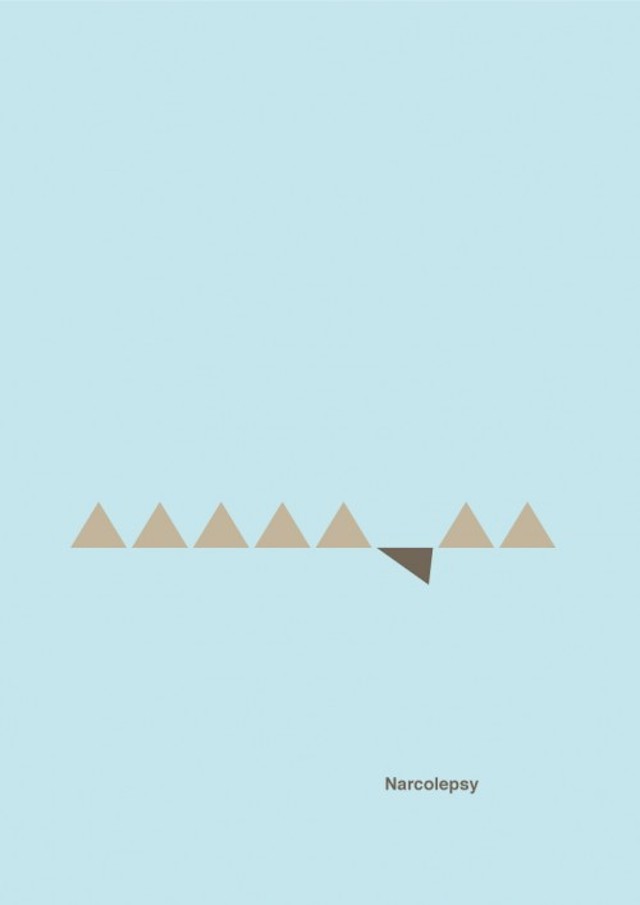

Like Christian Stoll who has put colors on psychology and emotions, Designer Patrick Smith managed to put graphic symbols on complex mental disorders. Through 7 minimalist posters and respecting precise color codes, we can decrypt the feelings of lack of understanding, division and isolation in certain psychological diseases.